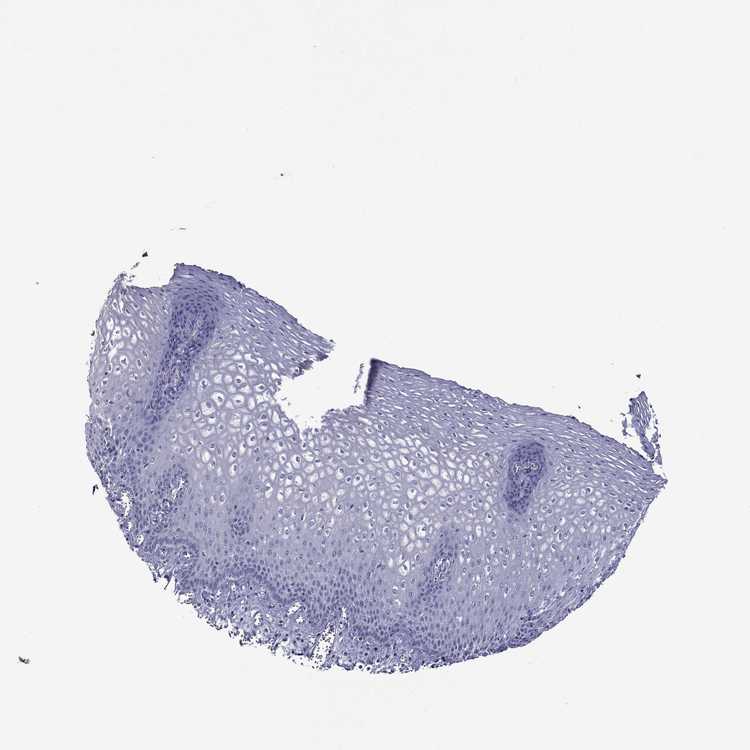

TISSUE PRIMARY DATA ESOPHAGUS Show tissue menu

ESOPHAGUS - Antibody stainingi

Antibody staining in the annotated cell types in the current human tissue is reported as not detected, low, medium, or high, based on conventional immunohistochemistry profiling in selected tissues. This score is based on the combination of the staining intensity and fraction of stained cells.

Each image is clickable and will lead to virtual microscopy that enables deeper exploration of all samples and also displays staining intensity scores, fraction scores and subcellular localization as well as patient and tissue information for each sample.

Antibody HPA041806Antibody HPA046289Antibody HPA075094

Squamous epithelial cells LowMediumNot detected